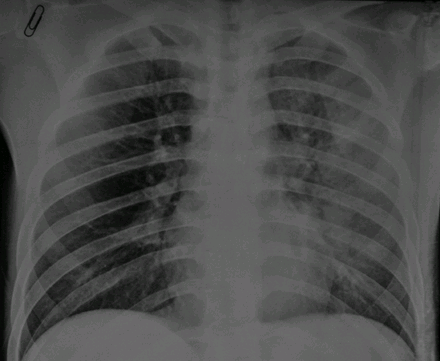

[H.1] Hình ảnh X-quang phổi một bệnh nhân nhiễm cúm A(H7N9)

Ảnh: Dennis KM Ip, http://www.bmj.com/content/346/bmj.f3693